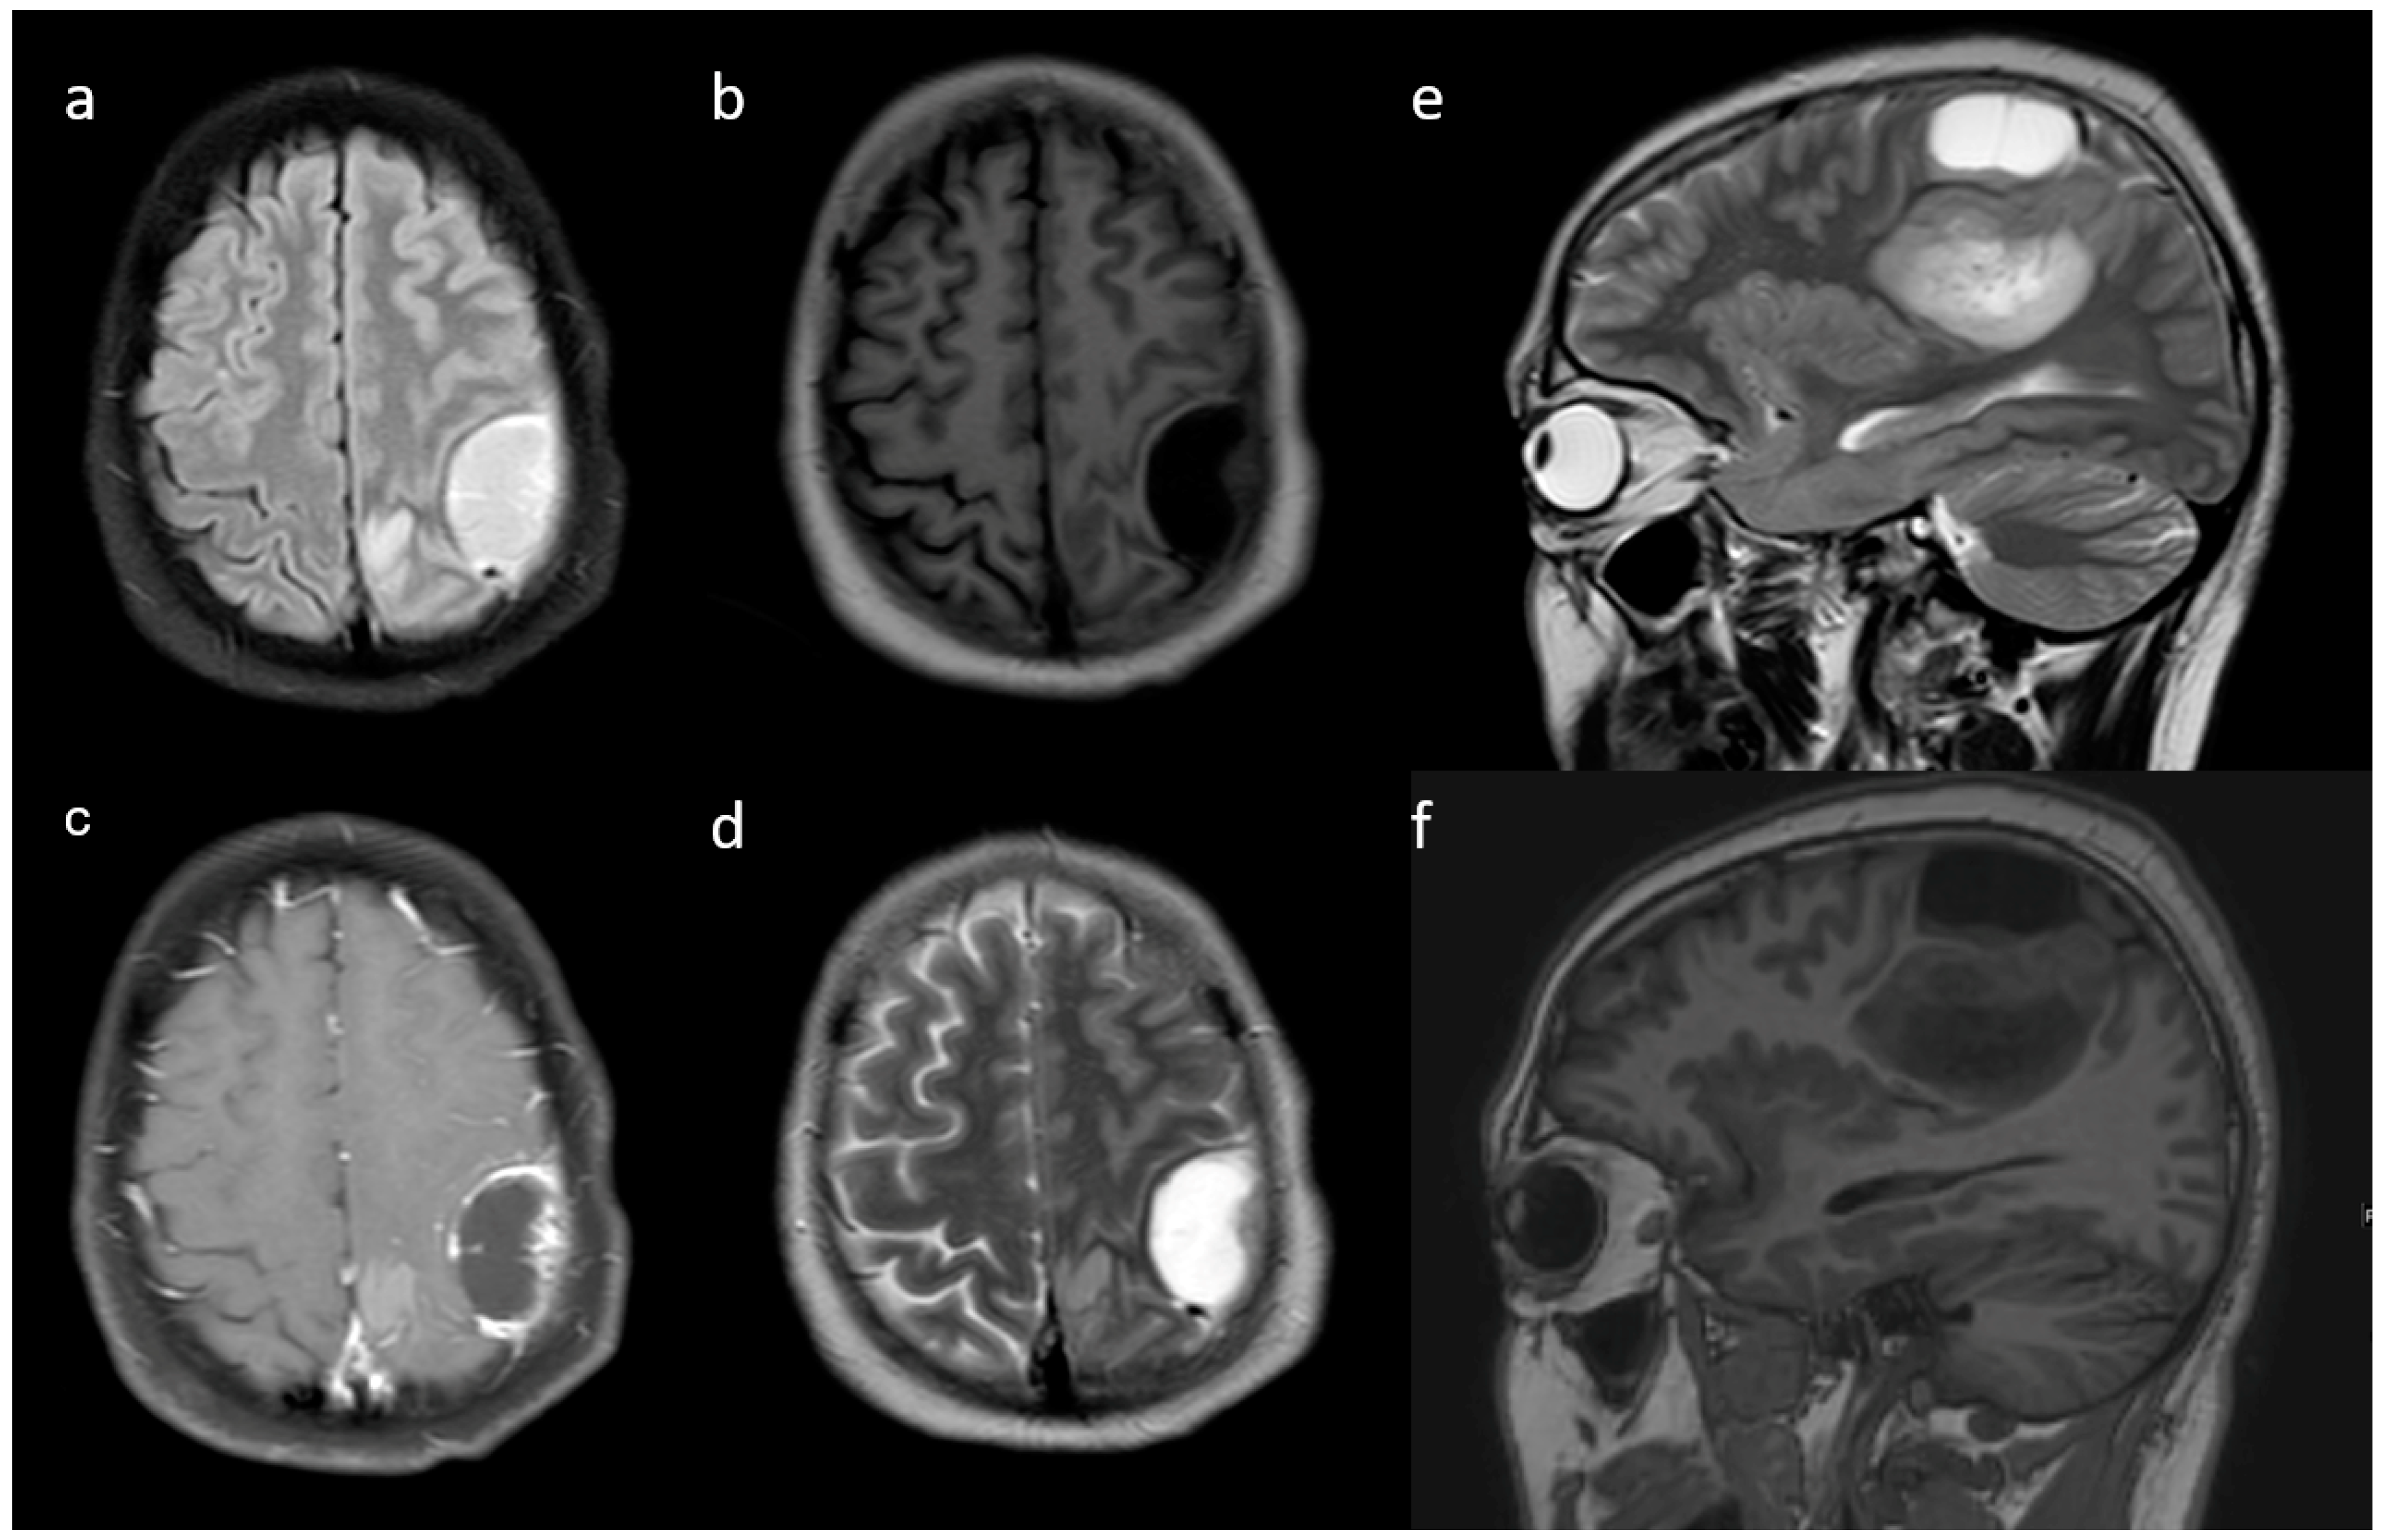

| Enhancement I | Mild | 9 (47.4) | 5 (3.9) | <0.001 |

| Moderate | 6 (31.6) | 25 (19.4) | ||

| Severe | 4 (21.1) | 99 (76.7) | ||

| Enhancement III | Rim | 6 (31.6) | 104 (80.6) | <0.001 |

| Nodular | 0 | 2 (1.6) | ||

| Patchy | 11 (57.9) | 13 (10.1) | ||

| Solid | 2 (10.5) | 10 (7.8) | ||

| Cysts * | No | 11 (57.9) | 115 (89.1) | 0.001 |

| Yes | 6 (31.6) | 14 (10.9) | ||

| Subcortical involvement | Involved | 18 (94.7) | 94 (72.9) | 0.044 |

| Not involved | 1 (5.3) | 35 (27.1) | ||